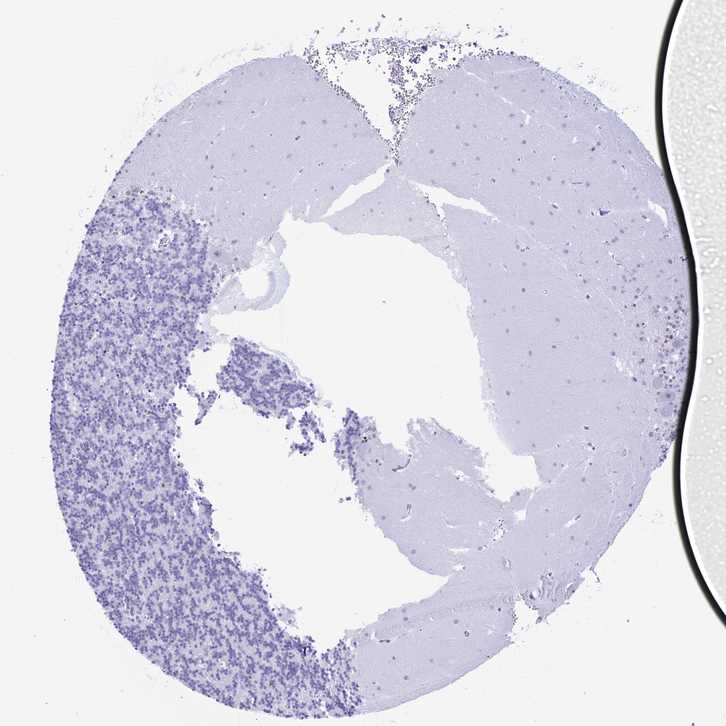

CEREBELLUM - Antibody stainingi

Antibody staining in the annotated cell types in the current human tissue is reported as not detected, low, medium, or high, based on conventional immunohistochemistry profiling in selected tissues. This score is based on the combination of the staining intensity and fraction of stained cells.

Each image is clickable and will lead to virtual microscopy that enables deeper exploration of all samples and also displays staining intensity scores, fraction scores and subcellular localization as well as patient and tissue information for each sample.

Antibody HPA044014

Purkinje cells Medium

Cells in granular layer Not detected

Cells in molecular layer Medium